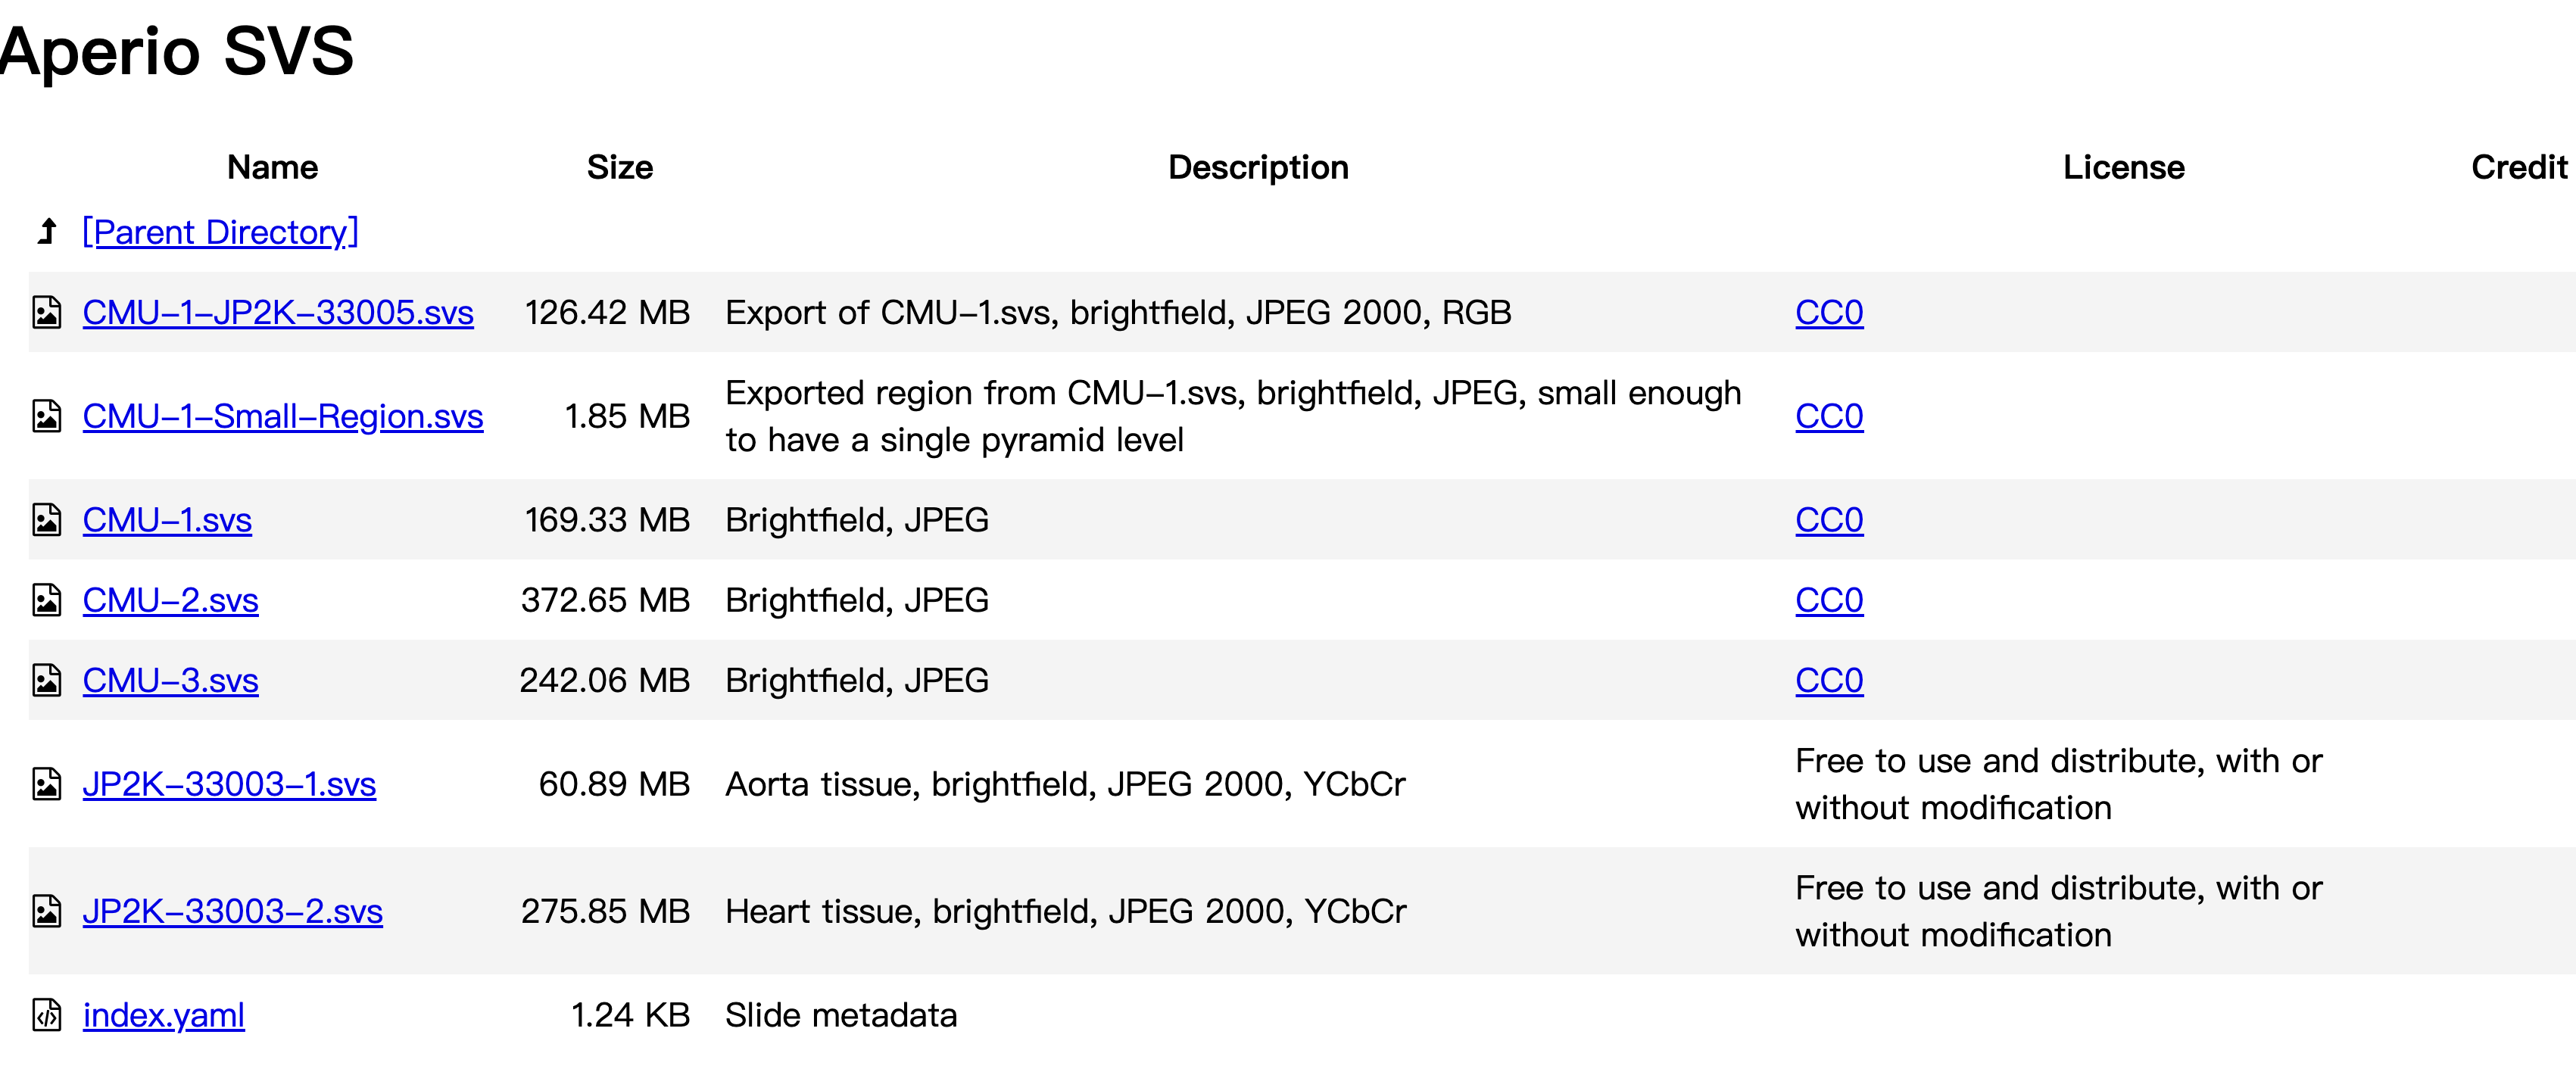

网页内容提供了一个由卡内基梅隆大学(Carnegie Mellon University, CMU)提供的Aperio扫描切片图像数据集。

这些数据集用于测试和展示OpenSlide库的功能。

- Parent Directory:这通常表示返回上一级目录的链接。

- CMU-1-JP2K-33005.svs:大小为126.42 MB,是一个以JPEG 2000格式、RGB色彩空间导出的CMU-1.svs图像。该图像是明场(brightfield)图像,并且是CC0许可,意味着可以自由使用,无需版权声明。

- CMU-1-Small-Region.svs:大小为1.85 MB,是从CMU-1.svs导出的一个小区域,以JPEG格式保存,足够小以至于只有一个金字塔级别。同样,它是CC0许可。

- CMU-1.svs:大小为169.33 MB,是一个明场JPEG格式的图像,也是CC0许可。

- CMU-2.svs:大小为372.65 MB,同样是CC0许可的明场JPEG格式图像。

- CMU-3.svs:大小为242.06 MB,也是CC0许可的明场JPEG格式图像。

- JP2K-33003-1.svs:大小为60.89 MB,是一个主动脉组织(Aorta tissue)的明场JPEG 2000格式图像,使用YCbCr色彩空间。该图像可以自由使用和分发,无论是否进行修改。

- JP2K-33003-2.svs:大小为275.85 MB,是一个心脏组织(Heart tissue)的明场JPEG 2000格式图像,使用YCbCr色彩空间。同样可以自由使用和分发,无论是否进行修改。

- index.yaml:大小为1.24 KB,包含切片的元数据信息。

这些数据集通常用于数字病理学研究,特别是在开发和测试图像分析算法时。由于它们是公开可用的,研究人员可以下载这些图像进行各种实验和验证他们的算法。

我们现在下载第三个图像。